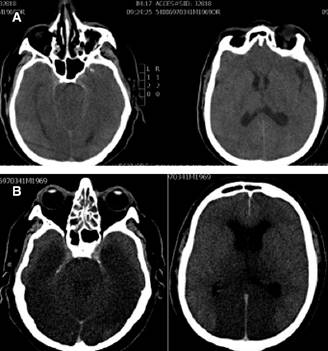

Al ingreso signos vitales de 162/108 mmHg, frecuencia cardiaca de 91 latidos por minuto, temperatura de 36 grados Celsius y 18 respiraciones por minuto. Neurológicamente integro, consciente, orientado, escala de coma de Glasgow de 15 puntos, pupilas isocóricas normorreflecticas, campimetría alterada en ojo izquierdo, no asimetría facial, gesticulación libre, fuerza conservada global extremidades torácicas y pélvicas 5/5, Babinski presente positivo en miembro pélvico izquierdo. Resto de la exploración sin anormalidades. La tomografía axial computarizada cerebral simple mostró estructuras supratentoriales e infratentoriales de densidad y morfología normal, sin identificar lesiones focales, zonas de hipodensidad que sugirieran eventos isquémicos, ni zonas de hiperdensidad que sugieran hematomas o desplazamientos de estructuras medias, sistema ventricular y espacios subaracnoideos sin datos de hidrocefalia, ni colecciones hemáticas en esa localización; estructuras óseas observadas se aprecian sin trazos de fractura (Figura 1A).

Figura 1: A) Corte axial de tomografía simple al momento del ingreso del paciente. Se muestran cortes a nivel de mesencéfalo y ventrículos laterales. Densidad y morfología normal, sin identificar lesiones focales, zonas de hipodensidad que sugieran eventos isquémicos, ni zonas de hiperdensidad que sugieran hematomas o desplazamientos de estructuras medias. Sistema ventricular y espacios subaracnoideos sin datos de hidrocefalia ni colecciones hemáticas. B) Corte axial de tomografía simple 24 horas después de su ingreso a unidad de cuidados intensivos. Se muestran cortes a nivel de mesencéfalo y ventrículos laterales. Zonas de hipodensidad sugiriendo infarto masivo con datos francos de edema cerebral generalizado.

La evolución clínica del paciente fue desfavorable, 24 horas posteriores a su ingreso presentó midriasis y arreflexia pupilar bilateral, por lo que se realizó una tercera tomografía de cráneo encontrando infarto masivo a nivel occipital con datos francos de edema cerebral generalizado (Figura 1B). En la exploración física subsecuente no se encontraron reflejos de tallo cerebral, razón por la cual se suspendió sedación y 24 horas después se realizó prueba de apnea. Los resultados de la prueba de apnea fueron: gasometría basal inicial con PCO2 de 43.3 mmHg y posterior a ocho minutos de PCO2 de 87.1 mmHg. Las gasometrías fueron tomadas de una línea arterial que se colocó con ese propósito. Tras la prueba de apnea positiva y una prueba auxiliar confirmatoria positiva (angiotomografía) se egresó al paciente a piso de Medicina Interna para cuidados paliativos.